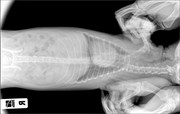

Коллапс трахеи форум